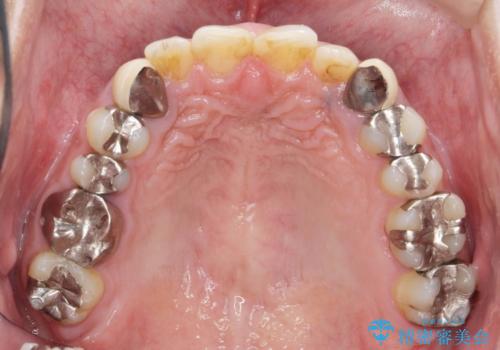

- 治療計画

- 長年虫歯の治療を受け続けたことで銀歯・コンポジットレジン修復だらけになってしまい、今後の見た目や歯を大切にするためにセラミック治療矯正治療を希望され来院されました。

マイクロスコープを用いた精密根管治療やセラミック治療、マウスピース矯正治療を一つの医院で行うことのできる当法人ならではの総合歯科治療を実践していきます。

- 約330万円 (セラミック治療 矯正治療 インプラント治療含む)費用は治療当時の料金となります